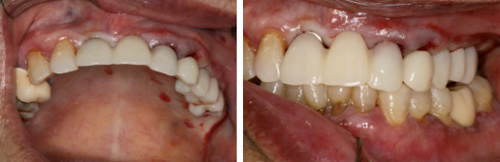

3、即刻修复

根据术前确定的种植方案制备临时修复义齿,手术过程中种植和修复一次完成。

4、最终修复美学效果显著改善

得益于术前的计算机辅助设计,种植修复后的美学效果可以预测,在种植方案规划中综合考虑咀嚼功能和美学功能的协调。